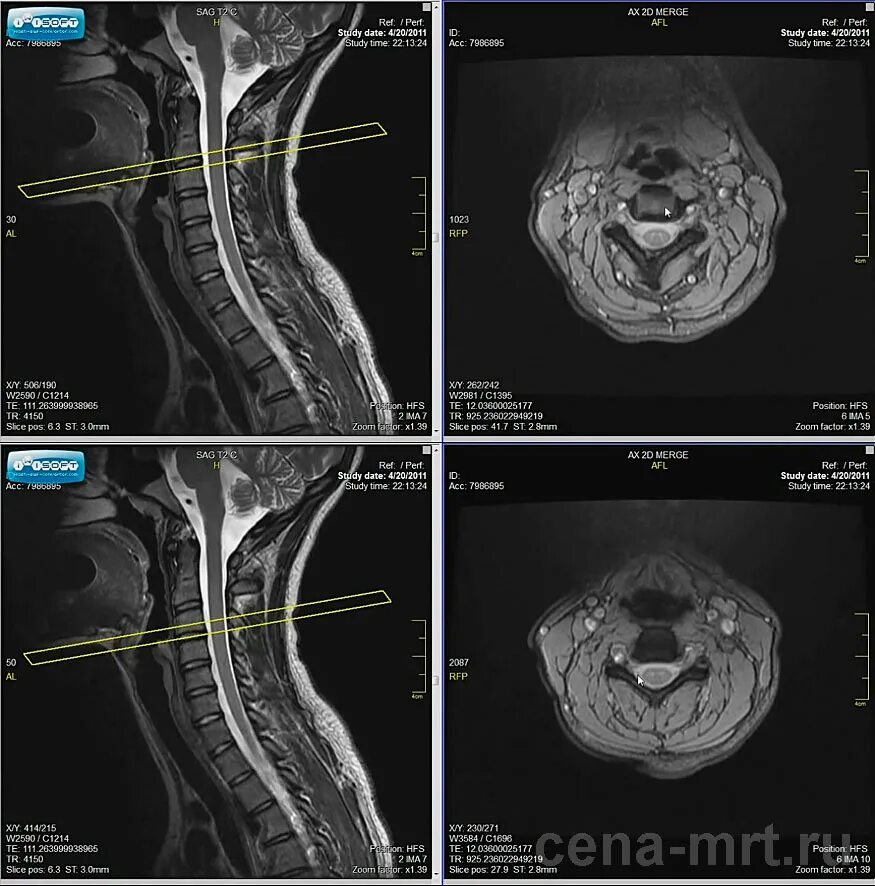

В шейном отделе мрт